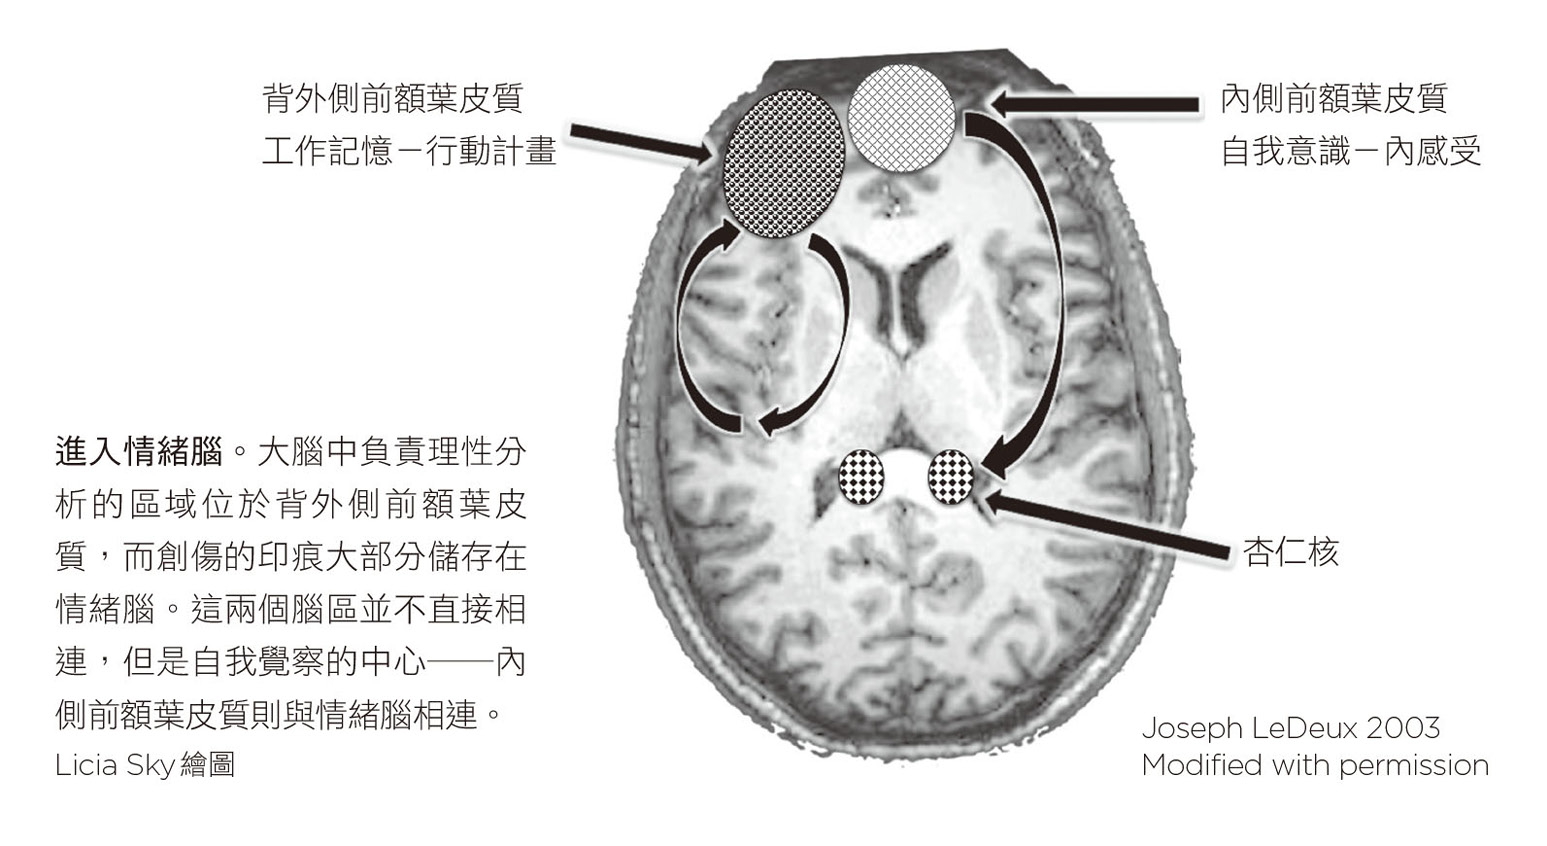

當然,本書「以身為度」的思考,以身體進行創傷的新思考,更是重要論點。作者指出「創傷的過程所銘刻下來的情緒和身體感覺,並不是以記憶的形式被感受,而是變成當前破壞性的身體反應。」作者的論點並非顯示受創記憶不重要,而是深刻地以身體感受領域說明,身體受創所承載的反應感受,會進而影響大腦激發和心智歷程,凸顯大腦、心智和身體在受創療癒中的互聯關係。事實上,就演化的機制而言,身體是可以記得受苦,而恐懼的命名就是這種受苦記憶的具現。恐懼,如同苦痛,是人類演化歷程的禮物,使得有機體可以預期危險、免於毀滅;而沒有能力去感受、記得苦痛,是一種無知的危險,可能導致「後創傷」(post-traumatic)經驗的呈現。如此,更容易使身體暴露在高風險環境,破壞性的身體反應也構成受創的惡性循環。人類處於各種災難變形的時代,面對各式警訊陰影的預期危機心理效應,受創者可能置身多重性的「後創傷」經驗裡,而身體反應的重組,更是重要機制。作者論證透過拼湊碎片以自我領導、填補空洞以創造結構、以神經回饋重設大腦迴路,逐漸安住身體,可以找到符合生活節奏和生存劇場的環境,發現屬於自己的聲音。本書作者的論點,使我們不但知道如何治療創傷,也逐漸知道如何預防,是重要貢獻。

影像圖上有一些令人費解的點和顏色,但活化程度最大的區域並不讓人意外,正是腦部中央偏右下方一個紅色的大區塊,即邊緣區,或稱情緒腦。目前已知強烈的情緒會活化邊緣系統,尤其是名為杏仁核的區域。杏仁核會在危險逼近時發出警告,並啟動身體的壓力反應。我們的研究清楚顯示,遭受創傷的人一旦接觸跟自己的特定經驗有關的影像、聲音或想法,如瑪莎的案例,即使事件已過了十三年,杏仁核都會發出警報。這個恐懼中樞被活化後會釋放壓力荷爾蒙和神經衝動,促使血壓上升、心跳加快,以及增加氧氣吸收,讓身體做好戰或逃的準備。1即使瑪莎很清楚自己正安靜地躺在掃瞄儀裡,但繫在手臂上的監測器仍記錄到這個狂亂激發的生理狀態。

我把杏仁核稱為大腦的煙霧偵測器,主要功能是辨識輸入的訊息是否與生存有關。11杏仁核的運作快速又自動化,附近的海馬迴則是協助將新訊息與過往經驗連結起來,回饋給杏仁核。杏仁核一感受到威脅,例如可能有輛車即將撞上來,或者有名路人看起來很危險,就會送出緊急訊號給下視丘和腦幹,並徵召壓力荷爾蒙系統與自主神經系統,精心協調動員全身的反應。杏仁核比額葉更快處理視丘送出的訊息,在我們意識到危險之前就已經決定輸入的訊息是否會威脅我們的生存。等到我們明白發生什麼事的時候,身體可能早已開始動作。

在創傷後壓力症中,杏仁核(煙霧偵測器)和內側前額葉皮質(瞭望臺)之間的重要平衡發生極大的變化,使人更難去控制情緒和衝動。神經影像研究顯示,當人們處於極度情緒狀態下,強烈的恐懼、哀傷和憤怒,都會使皮質下跟情緒有關的腦區活化量增加,並使額葉各部位的活動大幅減低,尤其是內側前額葉皮質。在這種情況下,額葉的抑制功能會故障,人也「失去理智」:他們可能會因巨大的聲響而受到驚嚇、因小小的挫折而暴怒,或一被碰觸便呆住不動。13

大腦有兩個系統與創傷的心理歷程有關,處理的分別是情緒的強度和脈絡。情緒的強度由煙霧偵測器(杏仁核)和其對手瞭望臺(內側前額葉皮質)共同決定,而某個經驗的脈絡與意義則由背外側前額葉皮質與海馬迴來決定。背外側前額葉皮質位於前腦的外側,而內側前額葉皮質則位於中間。大腦中線附近的結構負責處理你的內在經驗,大腦外側的結構則主要負責你和周遭環境的關係。